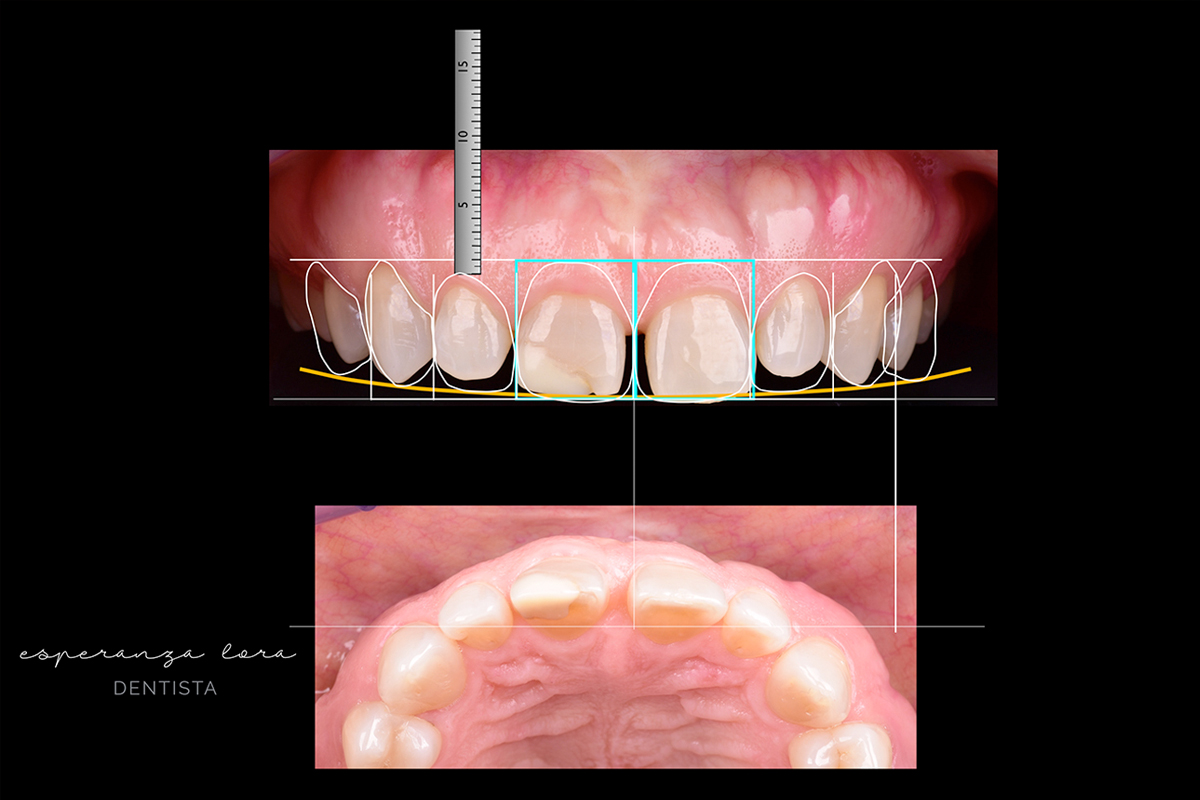

El Diseño Digital de Sonrisas consiste en una simulación mediante fotografías de cómo quedará la sonrisa del paciente que previamente hemos planificado con la ayuda de nuestra Radiografía 3D y atendiendo a la fisionomía del rostro del propio paciente.

Mediante una serie de herramientas digitales, determinamos todos los parámetros de la estética dental y facial, como son línea media, plano interpupilar, línea de sonrisa, plano oclusal o longitud de los dientes.

Todo esto lo transferimos a la zona intraoral para poder diseñar la forma, tamaño y posición dental con respecto a la ubicación ideal dentro de la cara y en armonía con ésta. También recogeremos vídeos del paciente, en los que podremos observar los gestos y expresiones de la cara para así diseñar una sonrisa armónica acorde con la cara y personalidad del paciente.

Tras este estudio, diagnóstico y planficación del tratamiento, realizaremos un prediseño digitalizado aproximado sobre cómo podría ser la nueva estética del paciente. Nos sentaremos con este último para conversar sobre las diversas opciones y elegir la mejor. Una vez tengamos la aprobación del paciente, transmitiremos toda esta información al laboratorio para que éste elabore un encerado de nuestra planficación en el modelo y así realizar una prueba en el paciente.

De esta manera, podremos apreciar en vivo cómo sería el resultado definitivo de la sonrisa. Esta prueba también la recogeremos en fotografía y vídeo con objeto de realizar una comparativa del antes y el después y es, entonces, cuando el paciente decide si quiere realizar dicho tratamiento. Se trata de una herramienta de diagnóstico y planficación perfecta porque nos permite mirar no sólo a los dientes sino al conjunto de la persona.